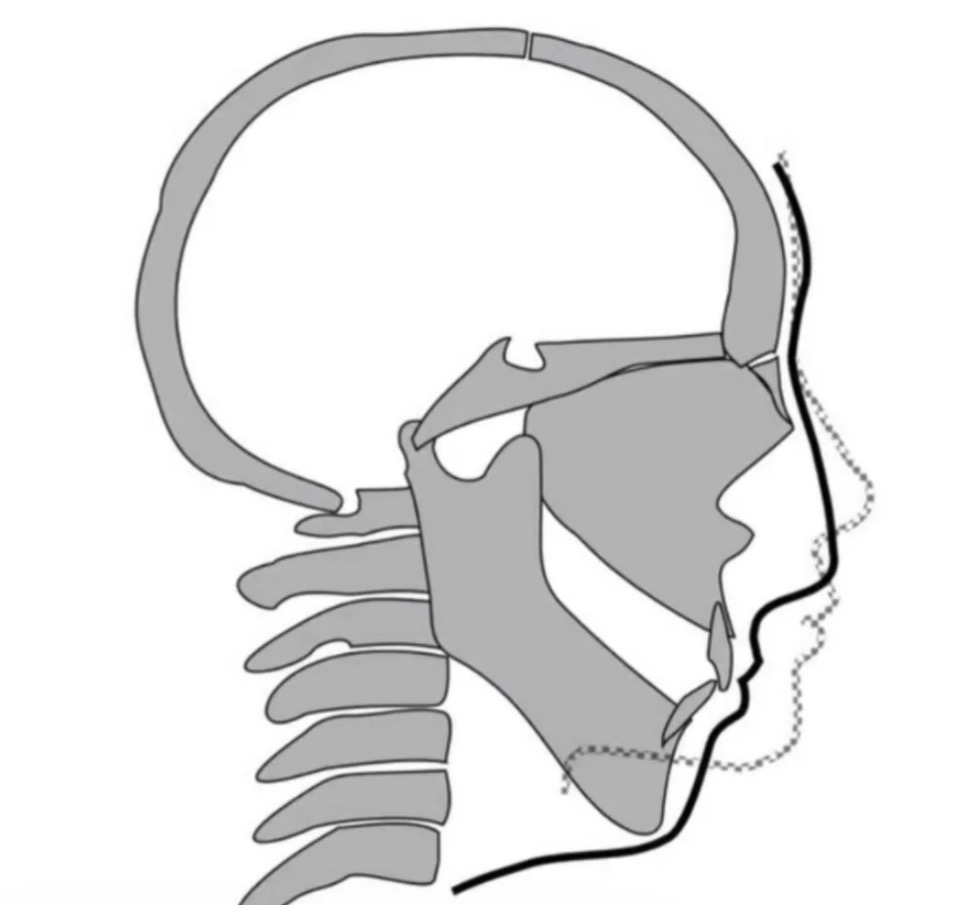

For reference here is what CCW can do, combined with a Bimax of course:

View attachment 4421320View attachment 4421319

Here is a skeletal graph of what it does:

View attachment 4421323

For reference here is what CCW can do, combined with a Bimax of course:

View attachment 4421320View attachment 4421319

Here is a skeletal graph of what it does:

View attachment 4421323